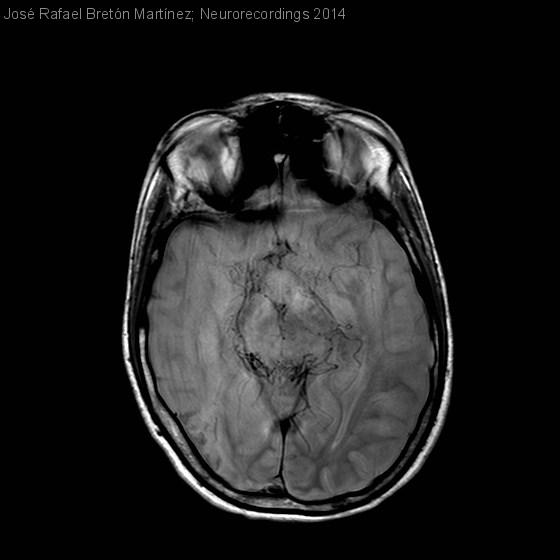

DÉFICIT FOCAL TRANSITORIO EN PACIENTE CON NEUROFIBROMATOSIS TIPO 1

Hombre | 15 años

Diagnóstico final: FENÓMENO DE MOYA-MOYA EN PACIENTE CON NEUROFIBROMATOSIS TIPO 1

Neurología: Patología cerebrovascular

Etiología: Malformación vascular